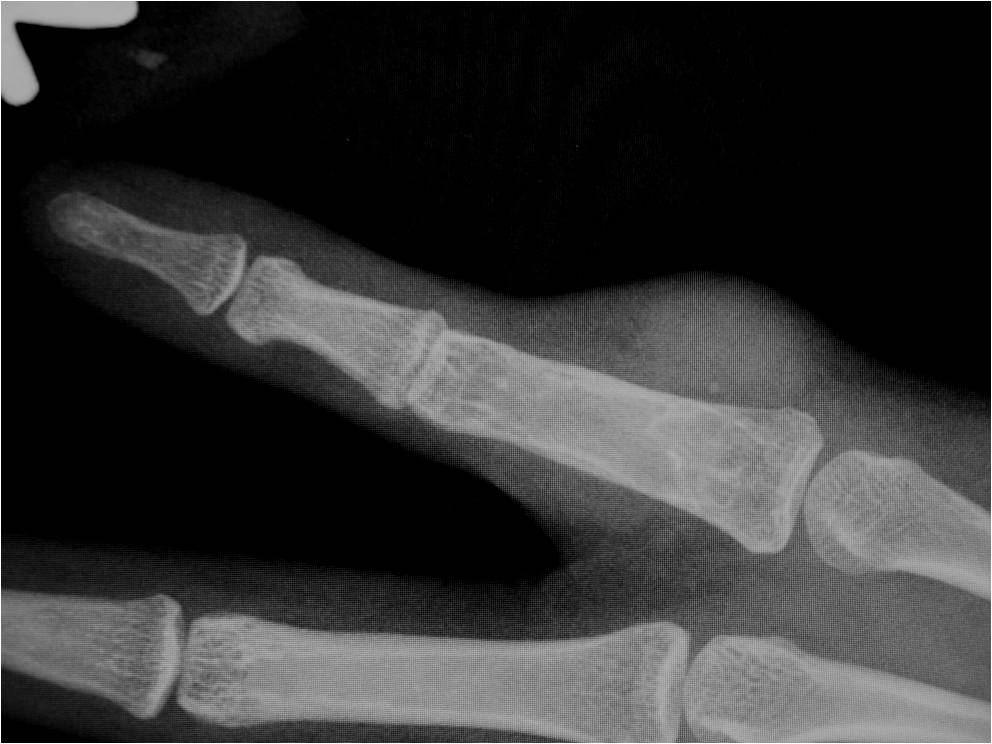

RADIOGRAPHIC PRESENTATION

Plain x-ray

• Soft tissue mass

• Pressure erosions in underlying bone in 15% of cases

• Calcifications are uncommon

Fig. 2-5: MR images of the hand with a giant cell tumor of tendon sheath shows a mass isointense to muscle on T1W and intermediate to high signal on T2W images. The lesion does not infiltrate the bone.